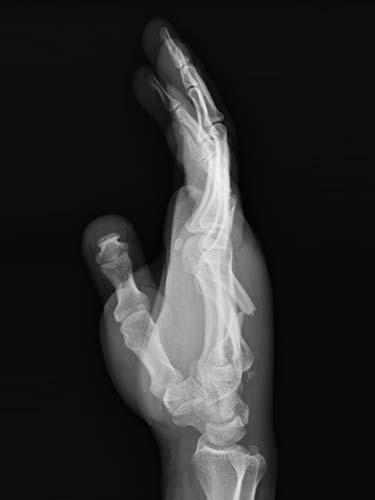

31 year old that suffered a broken bone in his hand while at work. Attempts were not possible at treating the patient without surgery because of the need to use his hand to help out with family obligations. He chose to have the hand treated with temporary wires that allowed him to help out with family obligations. The patient healed without any problems having regained full use of his hand.